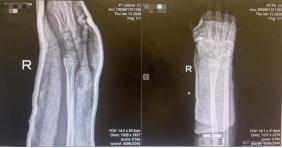

阳光讯(记者 郑亚雷 通讯员 曾雪琴)1月15日,9岁男童小洋因不慎摔伤致右腕部剧烈疼痛、活动受限4小时,被紧急送往西安市红会医院就诊。经影像学检查,确诊为右桡骨远端骨折合并骨骺滑脱,骨折类型复杂,复位难度较高。

患儿入院时携带的X线片显示,右桡骨远端骨皮质连续性中断,骨折端成角畸形,并伴有骨骺滑脱。此类涉及骨骺的儿童骨折对复位精度要求极高,既要恢复骨骼的正常解剖对位,以保障肢体功能及骨骼正常发育,又需最大限度避免对骨骺造成二次损伤,以免影响未来的骨骼生长,这给治疗带来了不小的挑战。

整个复位过程在团队的默契配合下顺利完成,术后患儿疼痛显著缓解,随即予以稳妥的外固定处理。复查X线片显示,骨折端对位对线明显改善,达到功能复位标准。安浩医生随后向家属详细交代了家庭护理要点、观察事项及康复指导,并安排次日返院复查。